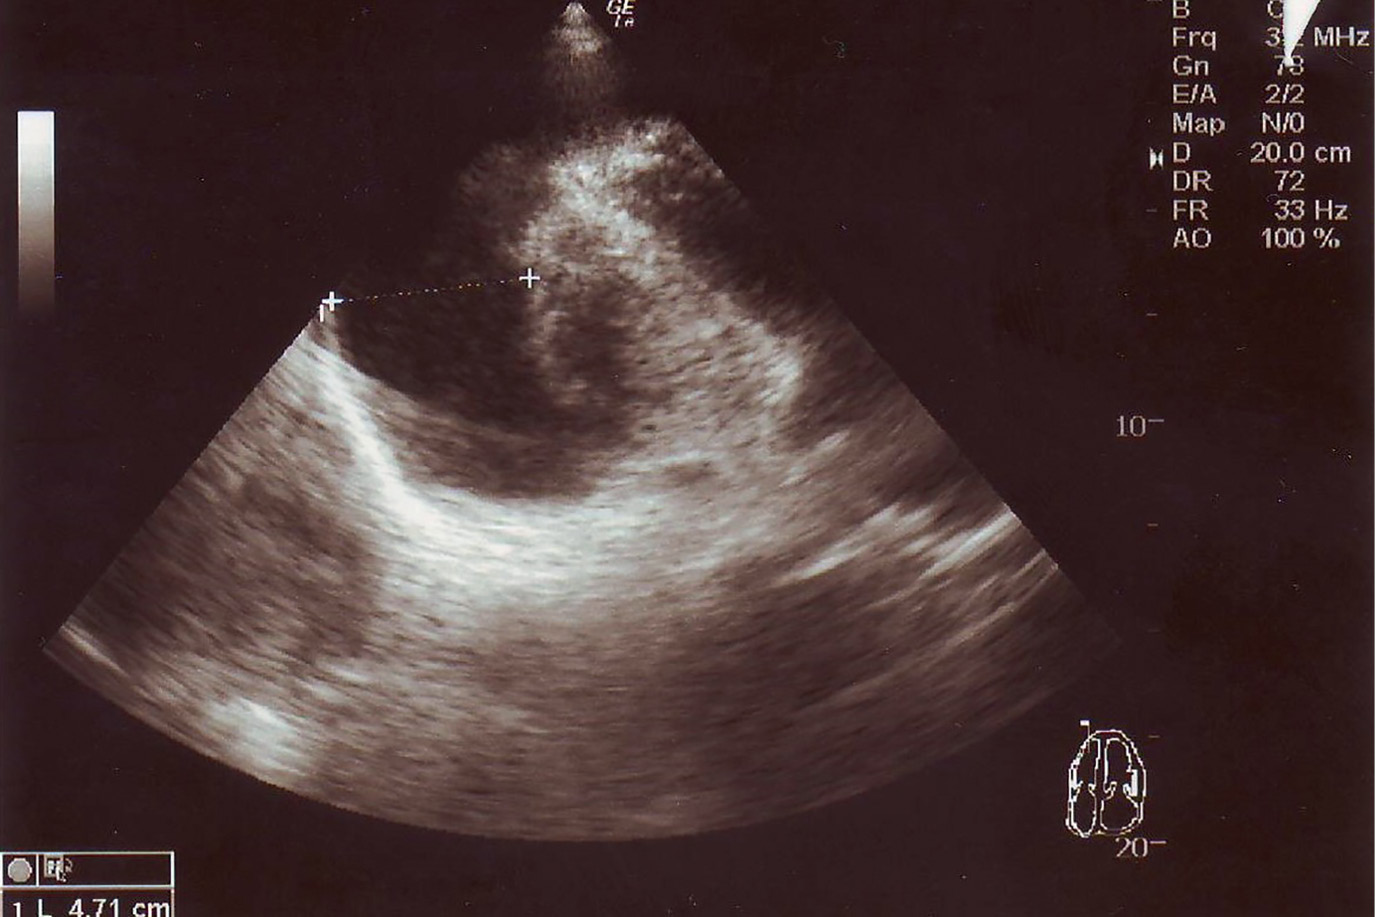

2. Рисунок 2. УЗИ сердца. Гидроперикард в области верхушки. | |

3. Рисунок 3. УЗИ сердца. Гидроперикард по задним отделам сердца. | |

4. Рисунок 4. УЗИ сердца. Гидроперикард за правыми отделами сердца. | |

РЕЗУЛЬТАТЫ. Перикардиальный выпот зарегистрирован у 9 человек (10,7%). Массивный выпот с сепарацией листков перикарда от 30 до 50 мм и угрозой тампонады был у 4 из 9 пациентов. Даже при большом объеме перикардиального выпота классические симптомы, такие как одышка, ортопноэ, боль в груди, чувство наполнения отсутствовали или были слабо выражены. Потребовалась дифференциальная диагностика с заболеваниями, сопровождающимися накоплением жидкости в полости перикарда. Показатели тиреоидного статуса позволили связать гидроперикард с декомпенсацией или впервые возникшим гипотиреозом. Заместительная терапия тиреоидными гормонами привела к исчезновению симптомов гипотиреоза и уменьшению гидроперикарда. При высоком риске тампонады у 3 пациентов терапия была дополнена перикардиоцентезом. Представлено клиническое наблюдение успешного лечения тиреоидными гормонами в сочетании с проведением перикардиоцентеза тяжелого впервые выявленного гипотиреоза с массивным перикардиальным выпотом.